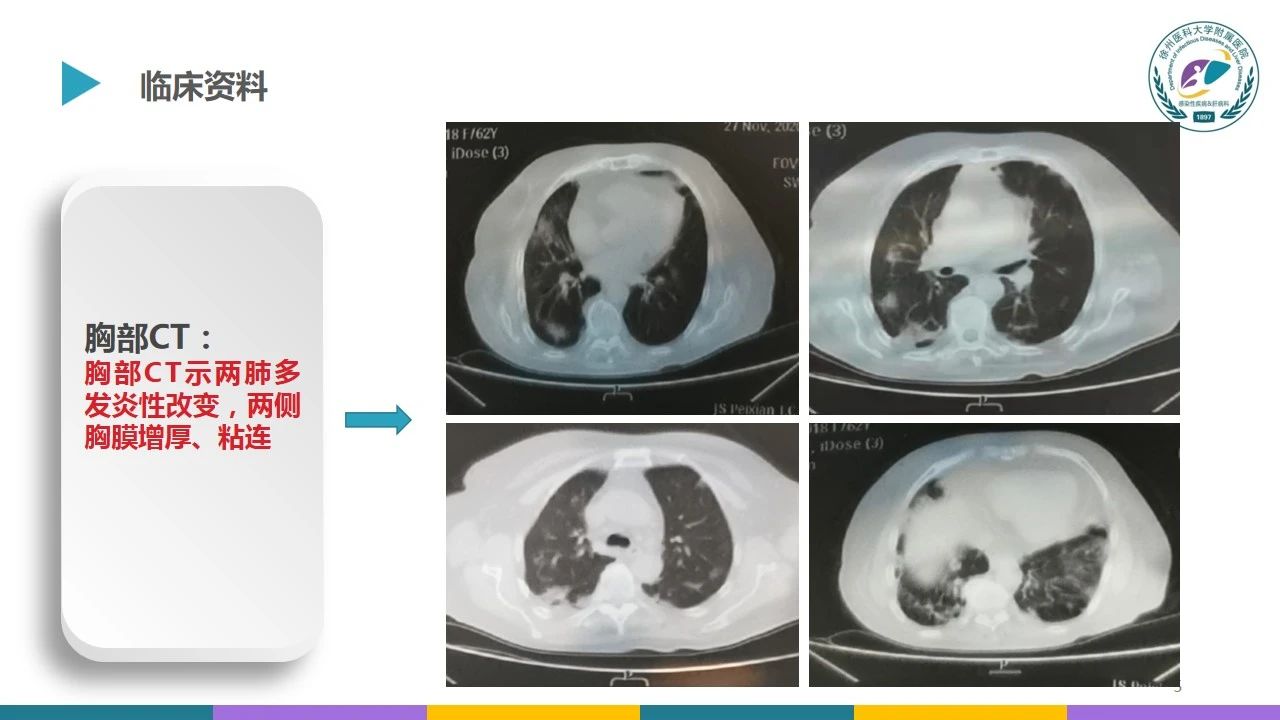

本文首发自徐医附院感染性疾病科